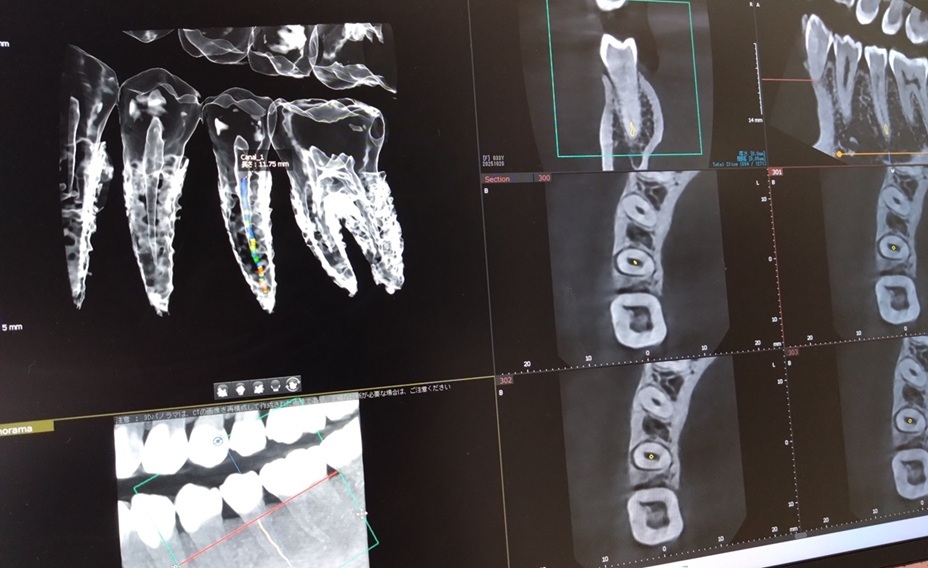

③CT撮影(エンドモード)

CT撮影を行うことで3次元的な情報を得ることができ今までわからなかった内容まで事前にわかるようになりました。

CT撮影に関しては保険診療でも認められており、彎曲根管(歯の根が大きく曲がっているもの)など治癒状態がよくない場合に撮影して診ることが可能になりました。

その為、今までは治療をしてからでないとわからなかった状態が、治療をする前に確認することも可能になりました。

CTも配備したことによりさらに「精密根管治療」の質が上がりました。